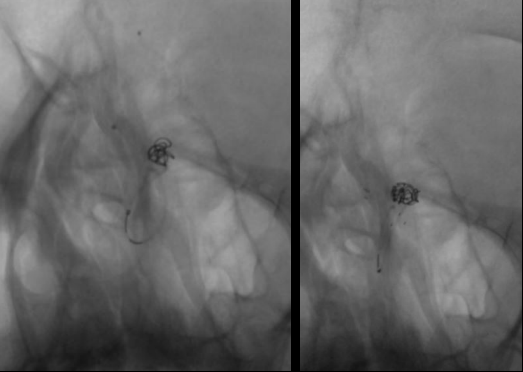

经右侧股动脉鞘,黑泥鳅导丝带领导引导管(Codman 6F Envoy DA)到达右侧颈内动脉岩段,微导丝(Synchro--14 0.014 in*200 cm)带领支架微导管(Excelsior SL--10)到达右侧大脑中动脉M2段,退出微导丝。微导丝带领弹簧圈微导管(Echelon10)到达右侧M1远端分叉处动脉瘤内,退出微导丝。经弹簧圈微导管填入弹簧圈(Codman 3 mm*4 cm)经支架微导管输送支架(Neuroform Atlas 3.0 mm*15 mm)并释放在M2段至M段中部,完全覆盖动脉瘤颈。继续经弹簧圈微导管依次填入弹簧圈数枚,间断造影确保右侧大脑中动脉及远端血流通畅。右侧颈内动脉造影确认:动脉瘤致密填塞,载瘤动脉通畅,手术结束。有侧股动脉穿刺处用血管封堵器封堵,并压迫器持续压迫。术后患者麻醉清醒,拔除气管插管,呼唤应答,对答切题,言语清楚,四肢肌力肌张力正常。安返病房。

患者在全麻下、多参数监护仪监测下行前交通动脉瘤经右侧颈内动脉支架辅助下栓塞术。全麻后,常规消毒销巾,采用改良seldinger技术穿刺右侧股动脉或功,置入6F动脉鞘。黑泥鳅导丝及多功能导管带领6F MPD导管达到右侧颈内动脉岩段,行造影见∶前交通动脉瘤,瘤体3.5 mm*5.1 mm。在路图引导下,徵导丝(Synchro 0.014 in*200 cm)带领弹支架微导管(SL-10)到右侧大脑前动脉A2段,退出微导丝。微导丝(Synchro 0.014 in*200 cm)带领弹簧圈微导管(eV3 Echelon-10)到达前交通动脉瘤体内,退出微导丝。经弹簧圈微导管填入首枚弹簧圈(Codman COMPLEX XTRASOFT3 mm*6 cm)成篮良好,在路图引导下在支架管内输送支架(Neuroform Atlas 3.0 mm*21 mm)并释放完全覆盖动脉瘤颈,造影可见支架打开良好解脱首枚弹备圈,沿弹簧圈导管继续填入弹簧圈(可见护理记录单)间断造影确保双侧大脑前动脉血流通畅。右侧颈内动脉造影确认∶前交通动脉瘤填塞致密,双侧大应前动脉血流通畅。手术结束。右侧股动脉鞘处用血管封堵器(Coxrds Exoseal 6F)封堵,并压迫器持续压迫。木后患者清醒。